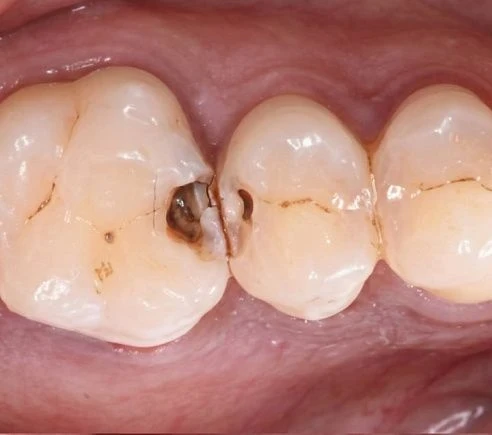

- Для реставрации жевательной поверхности зуба предпочтительным будет применение вкладки;

- Повреждение дентина кариесом или в результате механического воздействия

- Сильное разрушение коронки

- Трещины, сколы эмали